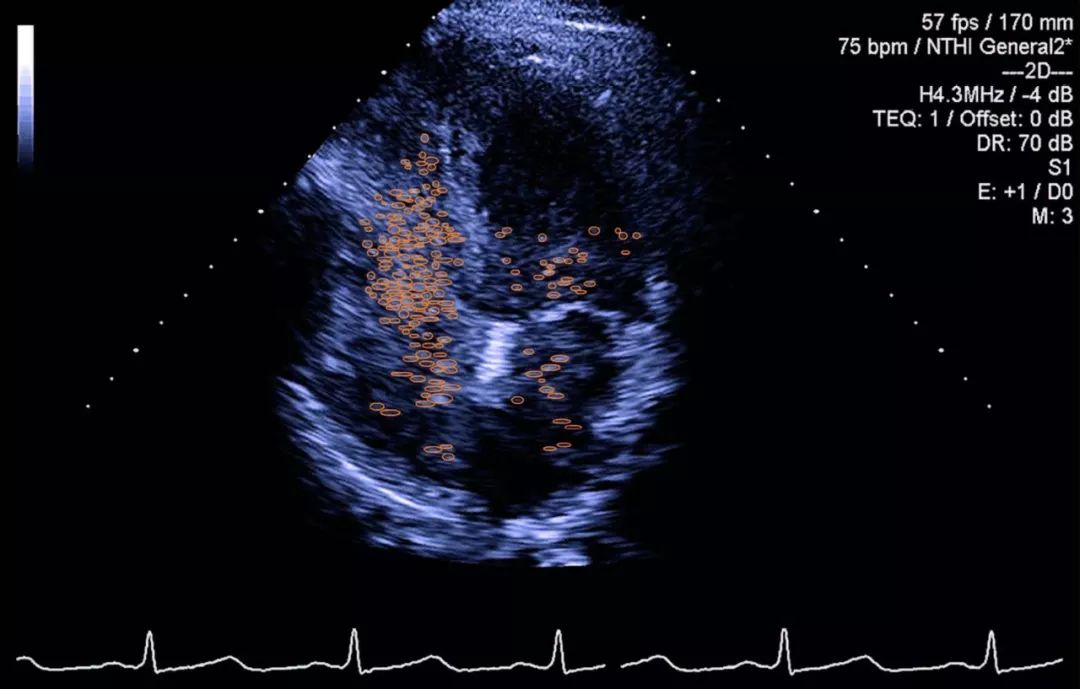

肝脏CT和超声显示肝硬化及门脉高压并侧支循环。为了确认诊断并进一步调查患者的病理生理学,进行了对比增强的经胸超声心动图,心脏左侧出现生理盐水气泡,表明肺内右至左分流(图)。

右心声学造影:采用手振生理盐水方法。具体配置方法为取两支10 ml注射器,一支抽取9 ml生理盐水和1 ml空气,通过三通开关将两支注射器相连,来回快速推注30次,使生理盐水和空气充分混合成含细小微泡的乳白色混合液,立即迅速推注。经食管右心声学造影选取能显示卵圆孔瓣的切面,经胸右心声学造影选取胸骨旁四腔心切面和心尖四腔心切面,视察valsalva动作后造影剂在心脏显影情况,造影过程中留存连续8~10个心动周期的动态图像。造影后逐帧回放并视察记录右心房充分显影后,进入左心房的微泡数量。为排除微气泡通过肺循环后回流入左心房形成的假阳性,选取前5个心动周期的结果,根据成像结果,选取微泡最多的切面评定分级。0级:0个气泡;1级:l~10个气泡;2级:11~30个气泡;3级:>30个气泡。